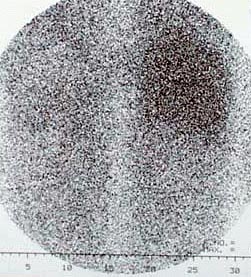

CaseFR01

- Age/Sex: 47F

- Chief Complaint: 後腹膜腫瘍の全身検索

- Clinical

Course: 約10ヶ月間心窩部痛を繰り返し,腹部CTで左後腹膜腫瘤が指摘された.手術で平滑筋肉腫の診断を得たが,骨シンチグラフィ異常を認めた.

- Lab. Data: BUN 8.1,Cr 0.61,Ca 8.1,Pi 2.8,CEA 正常,CA19-9

正常

- Images:

- X-CT, abdomen

- Bone scintigrams, Ant,

Lat

- Skull X-ray, XCT